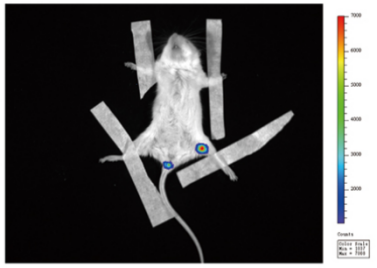

2.皮肤移植(干细胞治疗)领域的应用

(表皮移植4天后,IVScope 8500成像,曝光时间5min)